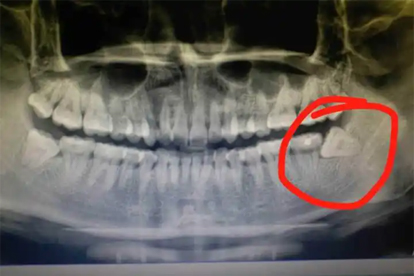

残留牙根超过3毫米或位于下颌神经管附近时,可能刺激周围组织引发慢性炎症,表现为持续肿痛、张口受限。此类情况需通过影像学检查评估风险,必要时行二次手术取出。若合并感染,需联合使用头孢克肟分散片和替硝唑片抗感染治疗,并避免用患侧咀嚼硬物。